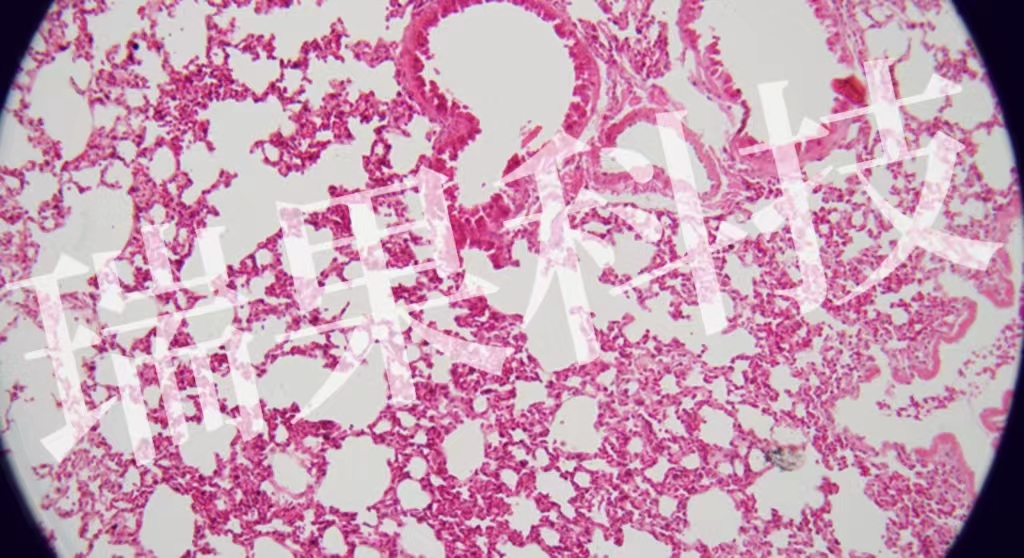

HE染色:蘇木精 - 伊紅染色法 ( hematoxylin-eosin staining ) ,簡(jiǎn)稱(chēng)HE染色法 ,石蠟切片技術(shù)里常用的染色法之一 。蘇木精染液為堿性 ,主要使細(xì)胞核內(nèi)的染色質(zhì)與胞質(zhì)內(nèi)的核酸著紫藍(lán)色 ;伊紅為酸性染料 ,主要使細(xì)

HE染色:蘇木精 - 伊紅染色法 ( hematoxylin-eosin staining ) ,簡(jiǎn)稱(chēng)HE染色法 ,石蠟切片技術(shù)里常用的染色法之一 。蘇木精染液為堿性 ,主要使細(xì)胞核內(nèi)的染色質(zhì)與胞質(zhì)內(nèi)的核酸著紫藍(lán)色 ;伊紅為酸性染料 ,主要使細(xì)胞質(zhì)和細(xì)胞外基質(zhì)中的成分著紅色 。HE染色法是組織學(xué)、胚胎學(xué)、病理學(xué)教學(xué)與科研中最基本、使用最廣泛的技術(shù)方法。

肺2-1-20x